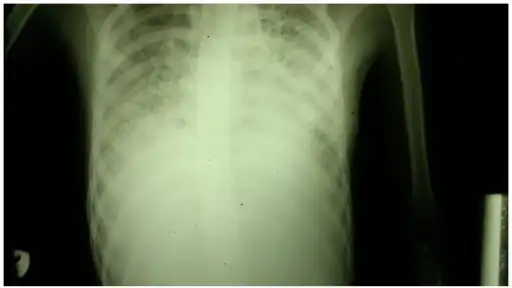

Pneumocystis pneumonia can present with interstitial lung disease, as seen in the reticular markings on this AP chest x-ray.

Chest radiography is usually the first test to detect interstitial lung diseases, but the chest radiograph can be normal in up to 10% of patients, especially early in the disease process.[17][18]

High-resolution CT of the chest is the preferred modality and differs from routine CT of the chest. Conventional (regular) CT chest examines 7–10 mm slices obtained at 10 mm intervals; high resolution CT examines 1–1.5 mm slices at 10 mm intervals using a high-spatial-frequency reconstruction algorithm. The HRCT therefore provides approximately 10 times more resolution than the conventional CT chest, allowing the HRCT to elicit details that cannot otherwise be visualized.[17][19]

Radiologic appearance alone, however, is not adequate and should be interpreted in the clinical context, keeping in mind the temporal profile of the disease process.[17]